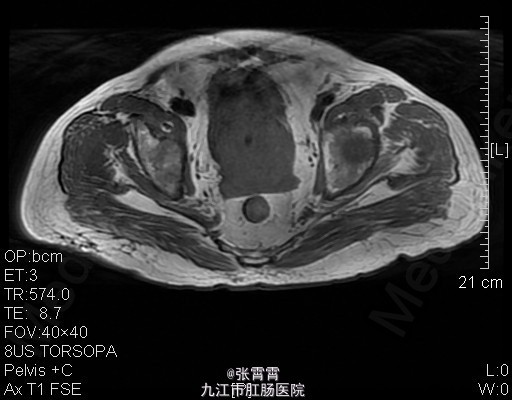

6、诊断:前列腺增生,膀胱结石,高血压 7、处理:住院后完善相关检查,盆腔MR平扫+增强扫描:1、前列腺增生并癌变,考虑侵犯前列腺包膜。2、慢性膀胱炎。3、双侧腹股沟区多发稍大淋巴结,考虑前列腺癌(早期)。诊断为前列腺增生。目前已排除手术禁忌证。予术前检查后行经尿道前列腺剜切术+耻骨上膀胱造瘘术+切开取石术,手术顺利,术后组织病理检查示前列腺增生,术后恢复顺利。